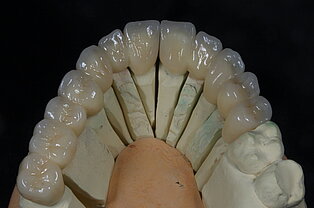

Keine Metalle im Mund